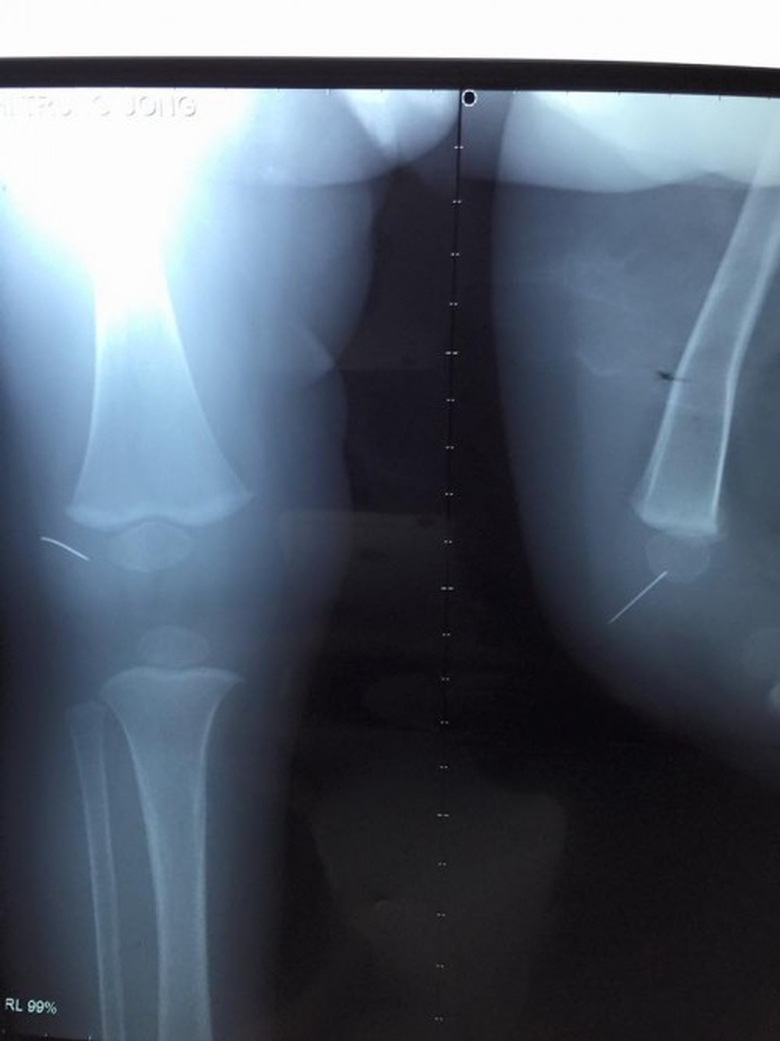

Hình ảnh chụp phim xác định dị vật kim khâu trong khớp gối của bệnh nhi |

Sau khi chụp phim, làm các xét nghiệm, bệnh nhi được chỉ định phẫu thuật. Theo BS Lê Tuấn Anh, khoa Chỉnh hình nhi, điều đáng nói là dị vật này rất mảnh và không cố định nên các bác sĩ đã rất khó khăn trong việc xác định vị trí và thực hiện phẫu thuật. Chính vì vậy khi mở bao khớp gối của bệnh nhi, bác sĩ đã không tìm thấy dị vật. Sau đó nhờ sử dụng máy X-quang tăng sáng, hỗ trợ định vị dị vật, các bác sĩ phát hiện đoạn kim đã găm vào xương bánh chè của trẻ. May mắn cuộc phẫu thuật đã thành công.